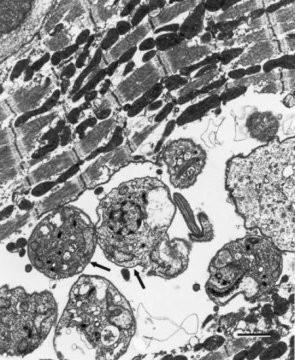

03:36 CH @ 17/06/2015Chagas là một trong những bệnh nhiệt đới phổ biến nhất ở châu Mỹ Latinh. Bệnh do ký sinh trùng Trypanosoma cruzi gây ra và đượcSự thay đổi gen nhanh chóng giúp ký sinh trùng sốt rét ẩn trong cơ thể người

04:49 CH @ 05/01/2015Một nghiên cứu về cách ký sinh trùng sốt rét (KSTSR) phát triển trong các tế bào hồng cầu của người cho biết KSTSR có thể thay đổiPhát hiện mới giúp chống lại bệnh ngủ châu Phi